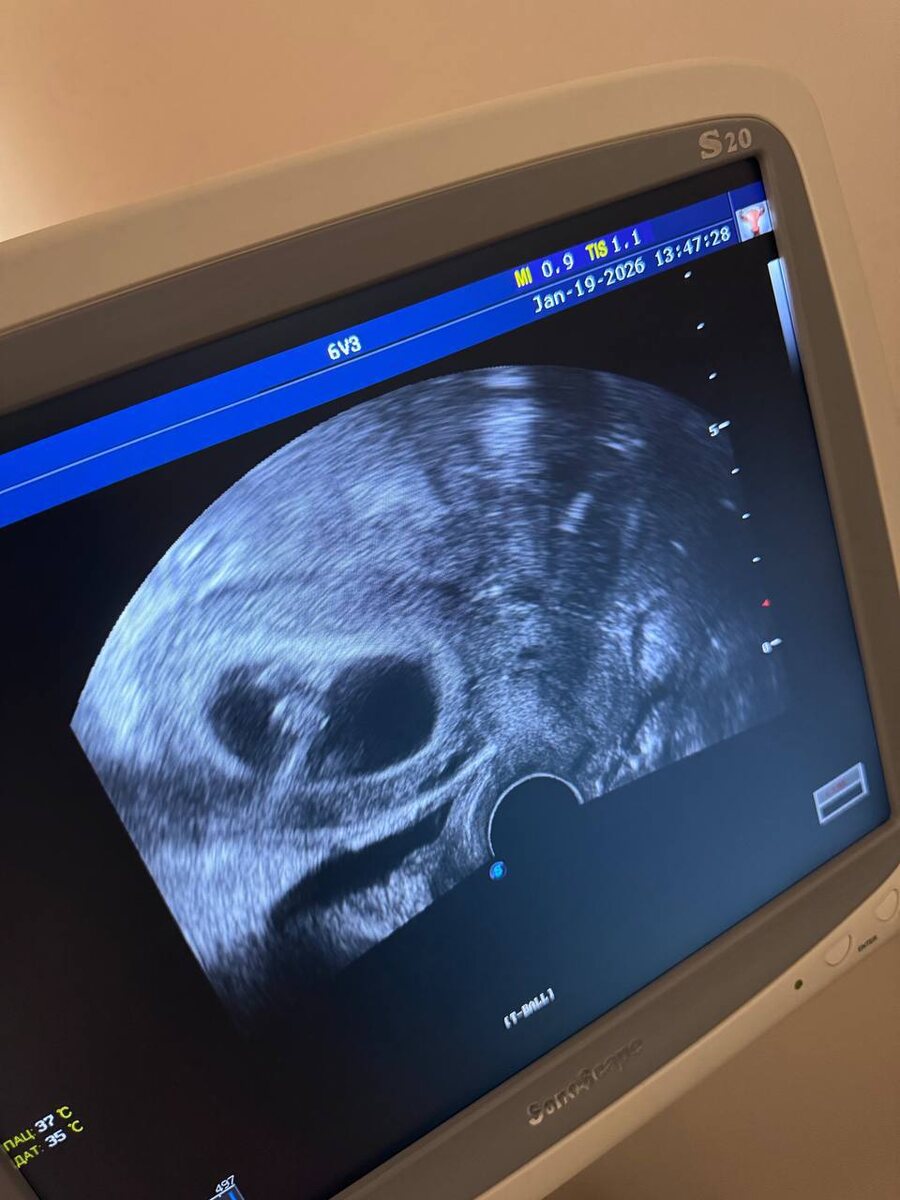

Беременность 7 нед, уже видим сердцебиение

. 💓 Протокол по всем канонам доказательной медицины : это был крио перенос в естественном цикле , эмбрион после пгта.